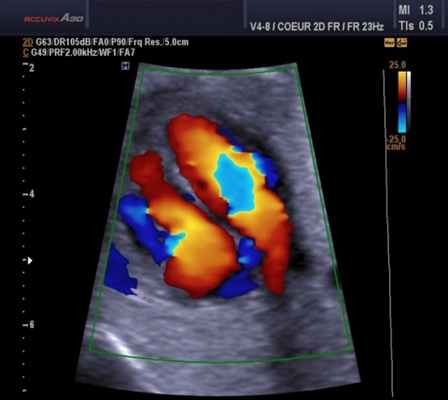

Эхокардиография (ЭхоКГ) с допплерографией и цветным картированием

Эходопплеркардиография — это инструментальный метод исследования сердца и кровеносных сосудов, при котором применяются ультразвуковые технологии.

Эходопплеркардиография — это инструментальный метод исследования сердца и кровеносных сосудов, при котором применяются ультразвуковые технологии. Как и при «рутинных» (М-режимной и двухмерной) эхокардиографиях (ЭхоКГ), данная методика использует высокочастотные звуковые волны, чтобы создать изображение сердца. Но помимо этого, чтобы определить скорость и направление кровотока, она дополняется эффектом Допплера.

Основные режимы визуализации, применяемые при УЗИ сердца

Ультразвуковое исследование сердца в основном используется для получения двухмерного изображения этого органа и близлежащих магистральных сосудов. А также с помощью этой методики можно оценить скорость и направление кровотока, что требует применение эффекта Допплера. В зависимости от того, как обрабатывается и отображается на мониторе эхо-сигнал, различают следующие режимы ЭхоКГ:

- Двухмерный (2D режим). На монитор выводится изображение сердца в разрезе (в двух измерениях). Данный способ является основным при визуализации этого органа, позволяет детально рассмотреть анатомические отклонения и аномальные движения миокарда, клапанов.

Для облегчения выявления турбулентного движения (завихрений) существует порог скорости, выше которого происходит изменение цвета (во многих аппаратах это зелены). «Мозаичный» узор на участке турбулентного потока позволяет легко установить регургитацию (смену направления движения), что помогает определить степень недостаточности клапанов.